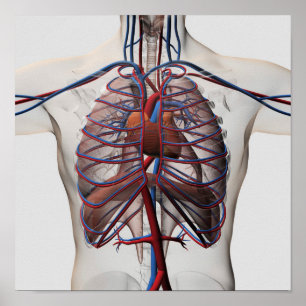

Poster 1833 interno da anatomia do coração do

Preço36,00 €

Póster O coração e as artérias bronquiais

Preço80,00 €